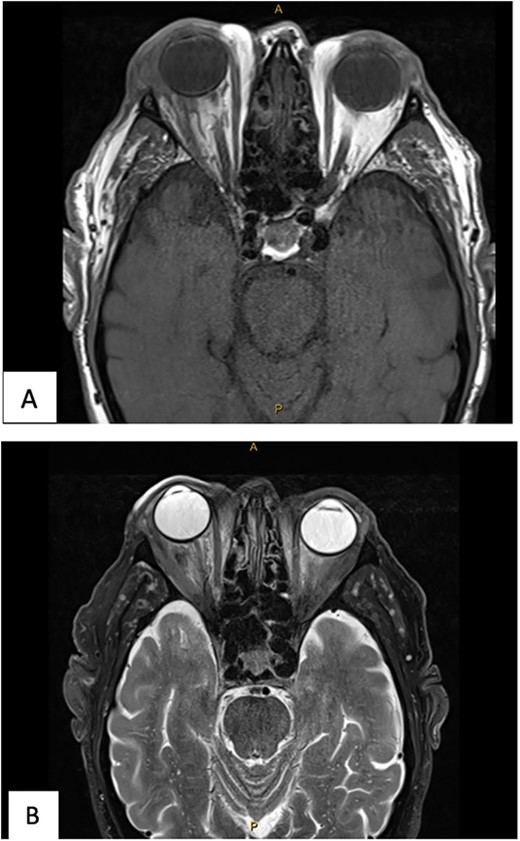

The patient underwent transconjunctival peritomy and drainage of the inferomedial abscess. However, vision regressed from hand movements to no light perception 5 days following initial drainage. Re-imaging of the orbit revealed a new retroorbital abscess accumulation superior-temporally (Fig. 4) that was also then drained. Both collections contained frank pus, and cultures also grew methicillin sensitive S. aureus, requiring a prolonged course of intravenous flucloxacillin and oral steroids. Subsequent MRI showed right lateral retroorbital abscess regression and less prominent retroorbital phlegmonous changes (Fig. 5). However, vision did not return to the patient’s eye.

Axial (A) and coronal (B) MRI T1 FS post contrast imaging demonstrating new, right sided posterosuperior, peripherally enhancing collection post drainage of previous collection.